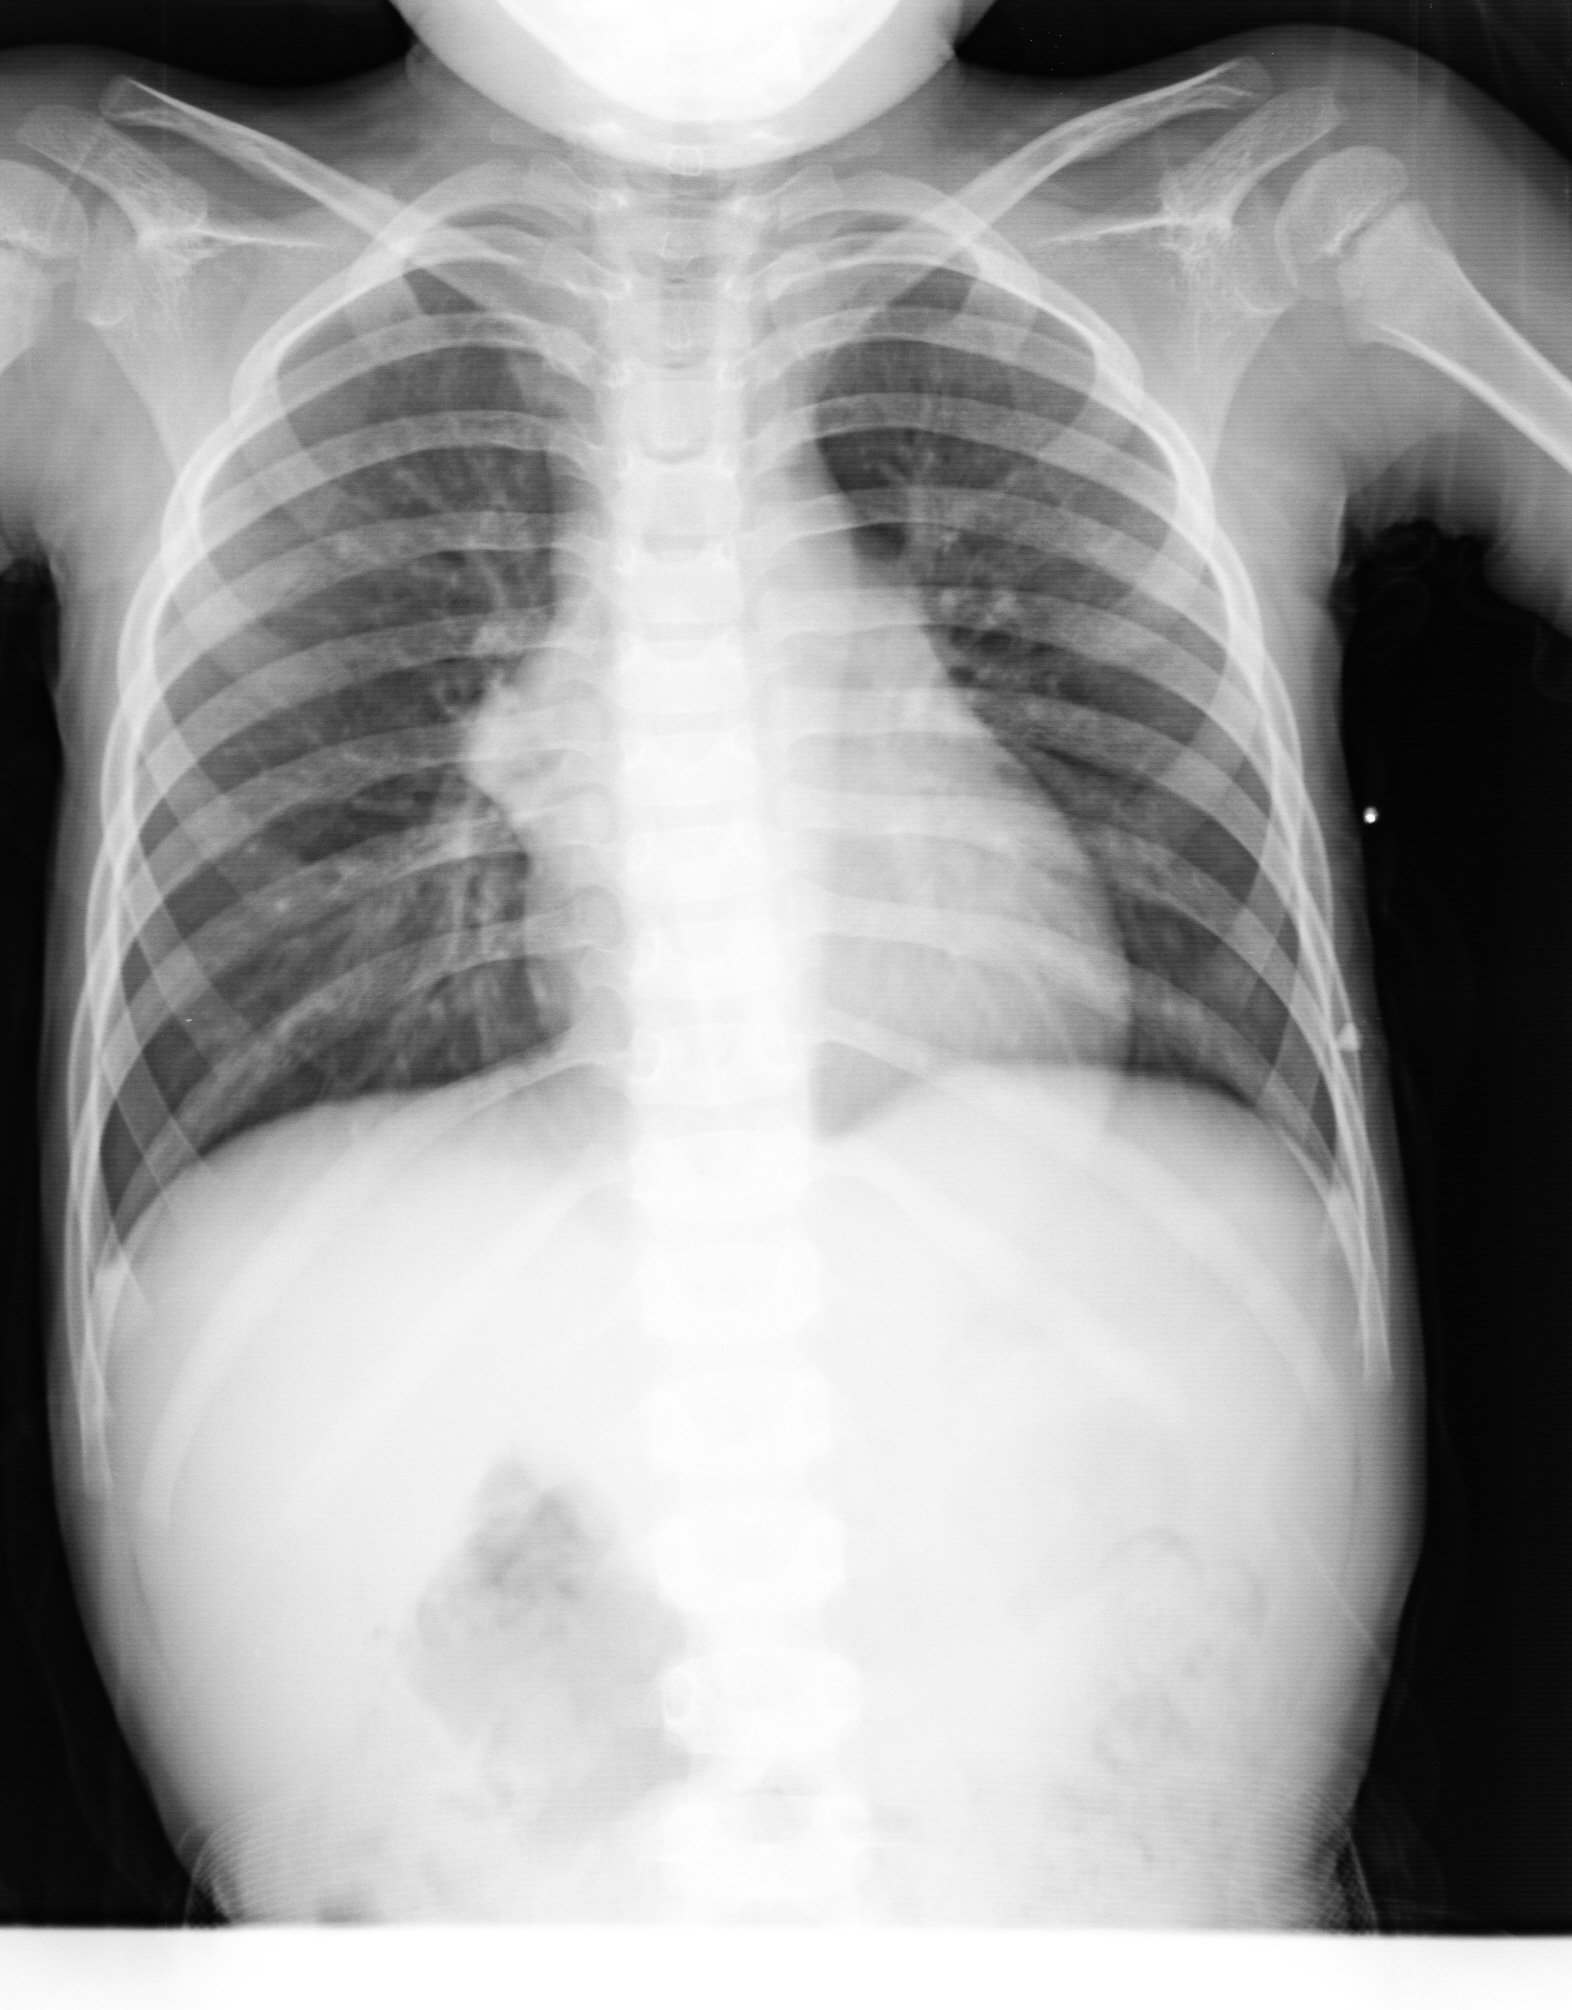

PED5372:小儿胸片

四岁,咳嗽半月余

考虑小儿支气管肺炎,右纵膈旁为胸腺“帆”征

右肺门区可见似三角形致密影外突。考虑:右肺门淋巴结核可能。建议CT检查。

两下肺中内带夹杂小点状阴影,可考虑小儿支气管肺炎,右纵膈旁为胸腺“帆”征,其他未见异常。